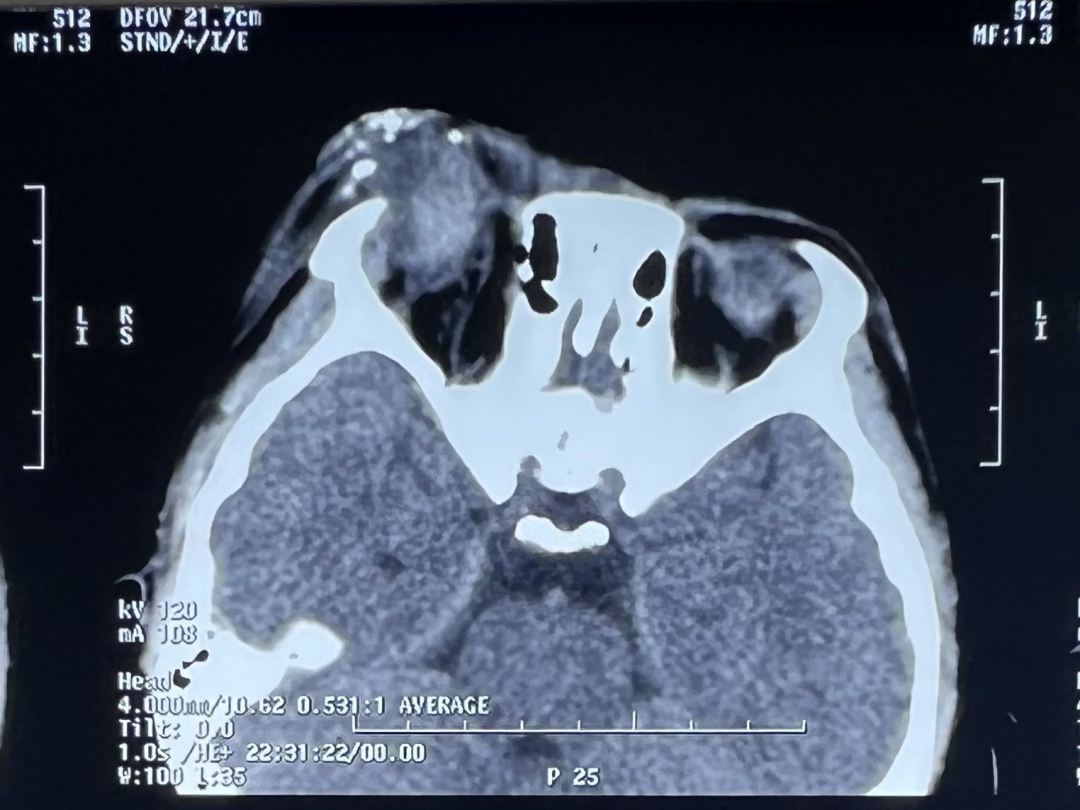

年仅11岁的小李同学小年夜在空地燃放爆竹时,遇到一个点火后没反应的“哑炮”,当他好奇地走上前去查看究竟时,突然发生了爆炸,鲜红的血液瞬间模糊了视野。当家长带着小李同学来到中山眼科中心就诊时,右眼已无光感,整个眼球破裂,眼睑裂伤,眼眶脂肪脱出,还有双眼皮肤不同程度的烧伤;而且CT检查显示右眼还残留大量散在高密度异物和多发眶骨骨折。虽然眼科急症团队第一时间对小李同学进行了紧急手术,经过长达数小时的抢救,取出了眼眶内的异物,缝合了眼球伤口,但由于伤情严重小李同学仍需面临后续多次手术的可能,视功能恢复的希望渺茫。

(小李就诊时的眼部情况和CT图像)烟花爆竹伤眼威力大